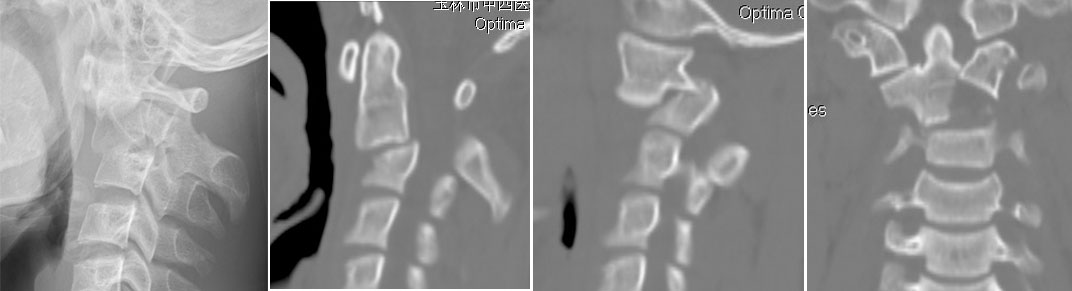

病例5  颈2.3水平椎管内肿瘤,后路减压固定肿瘤摘除术。

患者73岁,女性,颈2、3水平椎管内肿瘤。

患者术前四肢麻痛、乏力,四肢肌力4级。

患者术后四肢麻痛逐渐缓解,术后3个月四肢肌力恢复正常。